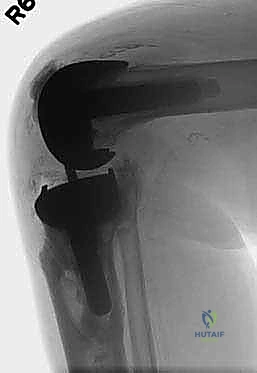

يعتمد الدكتور هطيف على أحدث تقنيات التصوير الطبي، بما في ذلك الأشعة السينية الرقمية (Digital X-rays) في وضعيات الوقوف، والتصوير المقطعي المحوسب (CT Scan) ثلاثي الأبعاد لتقييم حجم العظم المتبقي بدقة متناهية. كما يتم إجراء فحوصات دم شاملة وسحب سائل من الركبة (Aspiration) لاستبعاد وجود أي عدوى بكتيرية خفية.

1. التخدير والنهج الجراحي (Incision and Exposure)

يبدأ الإجراء بتخدير المريض (نصفي أو كلي بناءً على تقييم طبيب التخدير). يستخدم الدكتور هطيف الشق الجراحي القديم غالباً لتقليل الندبات. يتم فتح المفصل بحذر شديد، حيث يكون التحدي الأول هو التعامل مع الأنسجة الندبية الكثيفة الناتجة عن الجراحة السابقة وحماية الأوعية الدموية والأعصاب المحيطة.

2. إزالة المفصل القديم (Implant Extraction)

هذه هي المرحلة الأكثر دقة. الهدف هو إزالة الغرسات المعدنية والأسمنت العظمي القديم بأقل قدر ممكن من الضرر للعظم المتبقي. يستخدم الدكتور هطيف أدوات دقيقة متخصصة (مثل المناشير الدقيقة والأزاميل الرفيعة) لفصل المفصل القديم عن العظم بلطف، للحفاظ على كل ملليمتر من العظم الثمين للمريض.

5. استخدام السيقان المعدنية للتثبيت (Stem Fixation)

بما أن العظم العلوي للساق ضعيف، لا يمكن الاعتماد عليه وحده لتثبيت المفصل. لذلك، يتم إدخال ساق معدنية طويلة (Stem) متصلة بالغرسة الجديدة وتمتد إلى داخل القناة النخاعية لعظم الساق (Diaphysis). هذا الساق ينقل الضغط والوزن من منطقة المفصل الضعيفة إلى العظم القوي في منتصف الساق، مما يضمن ثباتاً ميكانيكياً فائقاً.